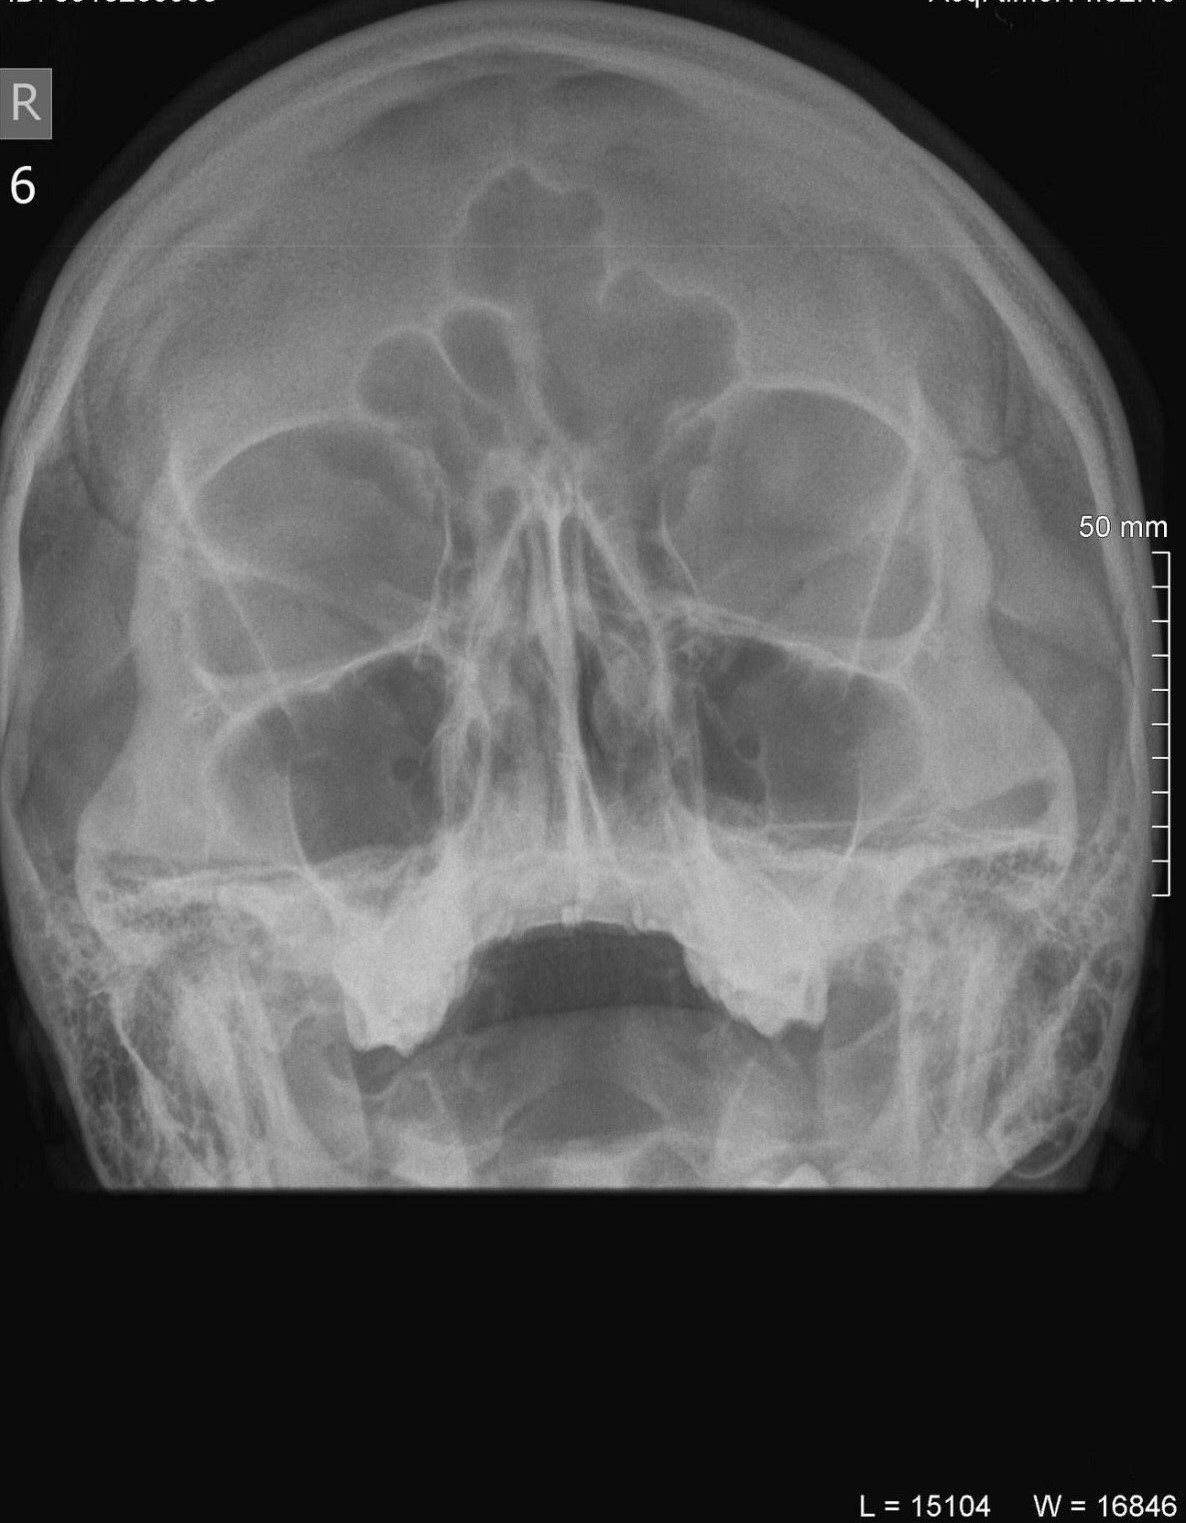

Може ли да ми помогнете с резултатите на тези изследвания? Пуснати са по повод често боледуване последните около 3 месеца. В момента съм на антибиотик Аугментин 9ти ден и въпреки него онзи ден отново вдигнах температура, която поддържах цял ден.

, но си мисля, че може да имаш двустранен синузит.